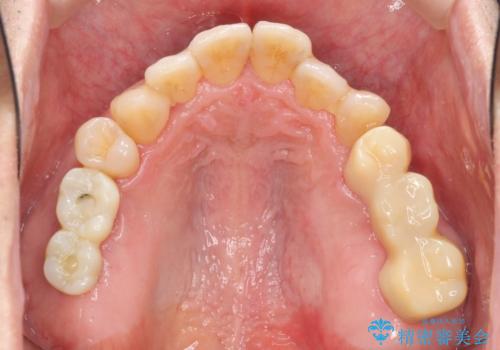

全顎的治療について

工程も多く、治療期間も長くなりがちですが、しっかりと通っていただいたおかげで安定した噛み合わせで食事を楽しむことができるようになりました。

メンテナンスも定期的に行うことで安定した状態を保っています。